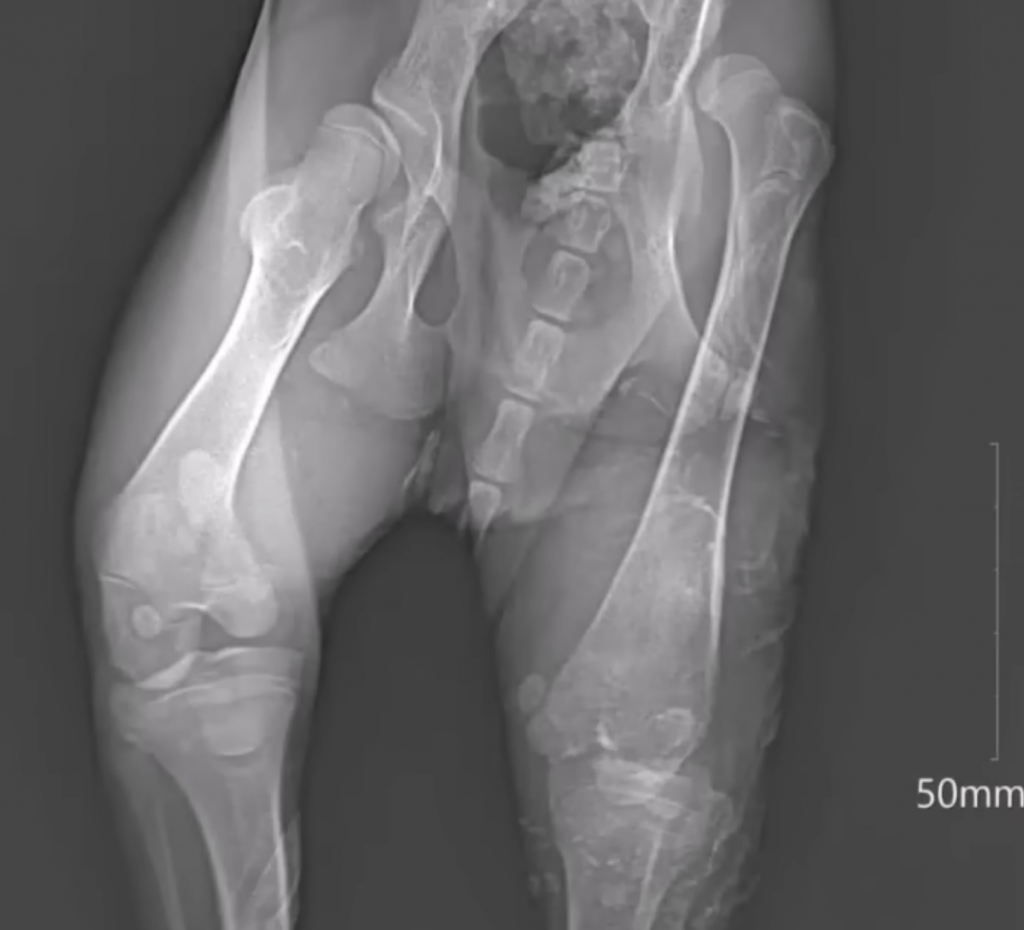

What the X-Rays Revealed

X-rays revealed a heartbreaking truth.

Multiple fractures.

Severe deformities.

Old injuries that had never healed.

These wounds weren’t recent. They told the story of long-term suffering—pain endured in silence, without treatment or comfort.

The veterinarian spoke quietly. Bonbon was in critical condition. Even with medical care, survival was uncertain.